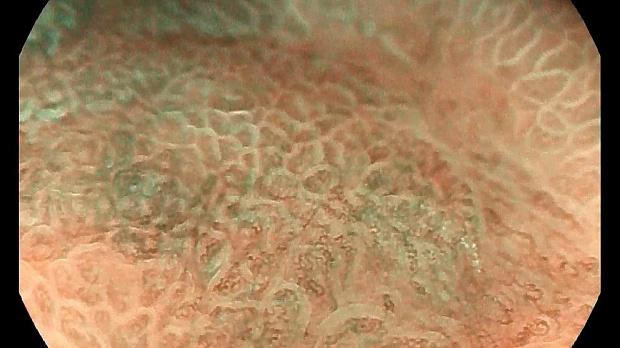

EarlyGastricCancer_3 – осмотр в белом свете, визуализируется нерегулярность окраски и изменения рисунка. Изменения неспецифичны.

Иллюстрация №3: осмотр в белом свете, визуализируется нерегулярность окраски и изменения рисунка. Изменения неспецифичны.